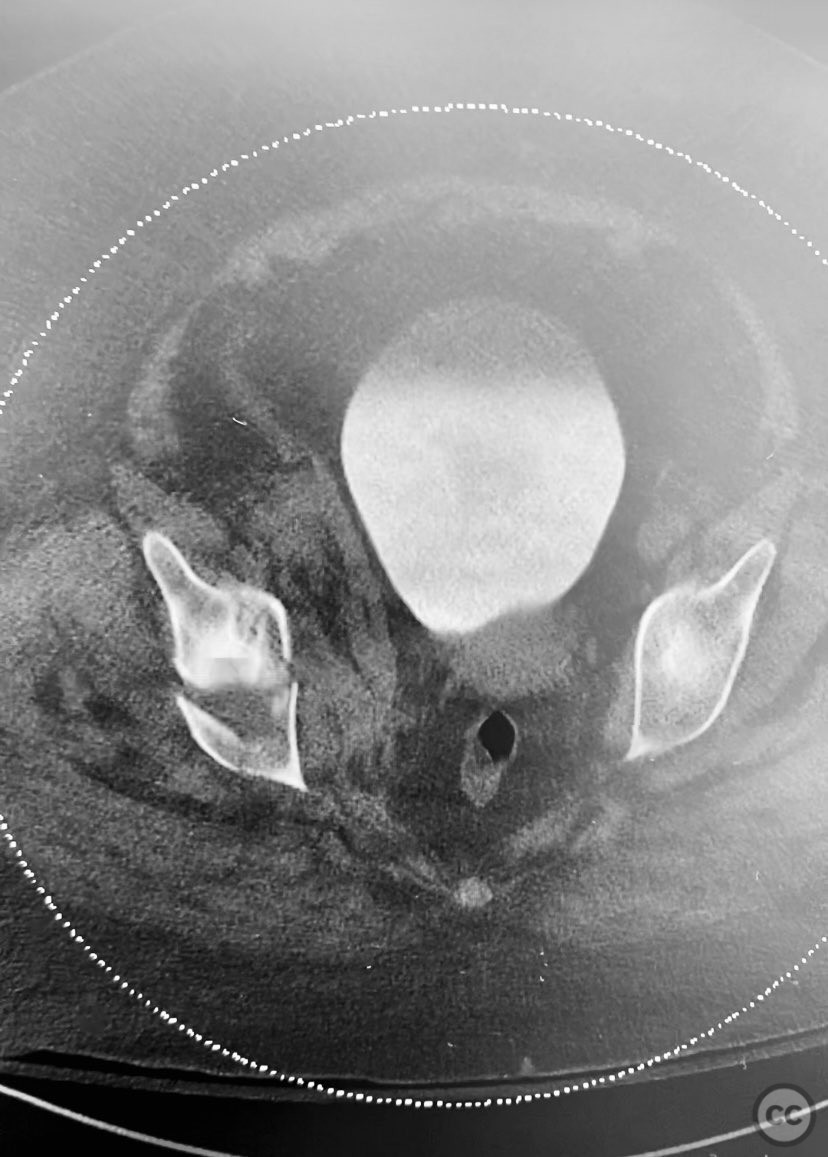

Clinical and radiological findings:  The patient is morbidly obese and sustained an unstable, displaced posterior column/posterior wall (PC/PW) acetabular fracture. Axial computed tomography images revealed a 2x2x1.5 cm pyramidal chondrocancellous articular fragment wedged in the fracture plane near the incisura ischiadica major (greater sciatic notch). Surface-rendered reconstructions further delineated the fracture morphology and fragment position. Obesity was noted to complicate all aspects of management, including anatomical localization, intraoperative imaging, and soft tissue handling.

Planning remarks:  The preoperative plan involved open reduction and internal fixation of the posterior column and posterior wall fragments, with retrieval and anatomic reduction of the intra-articular chondrocancellous fragment. A Kocher-Langenbeck approach was selected for direct access to the posterior acetabulum. Contoured plates and screws were prepared for definitive fixation.